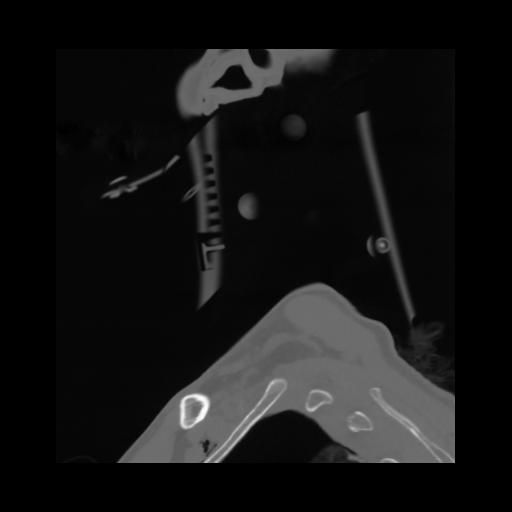

14 P.BLANDAS,,Sagittal,2.000,P.BLANDAS,Sagittal,